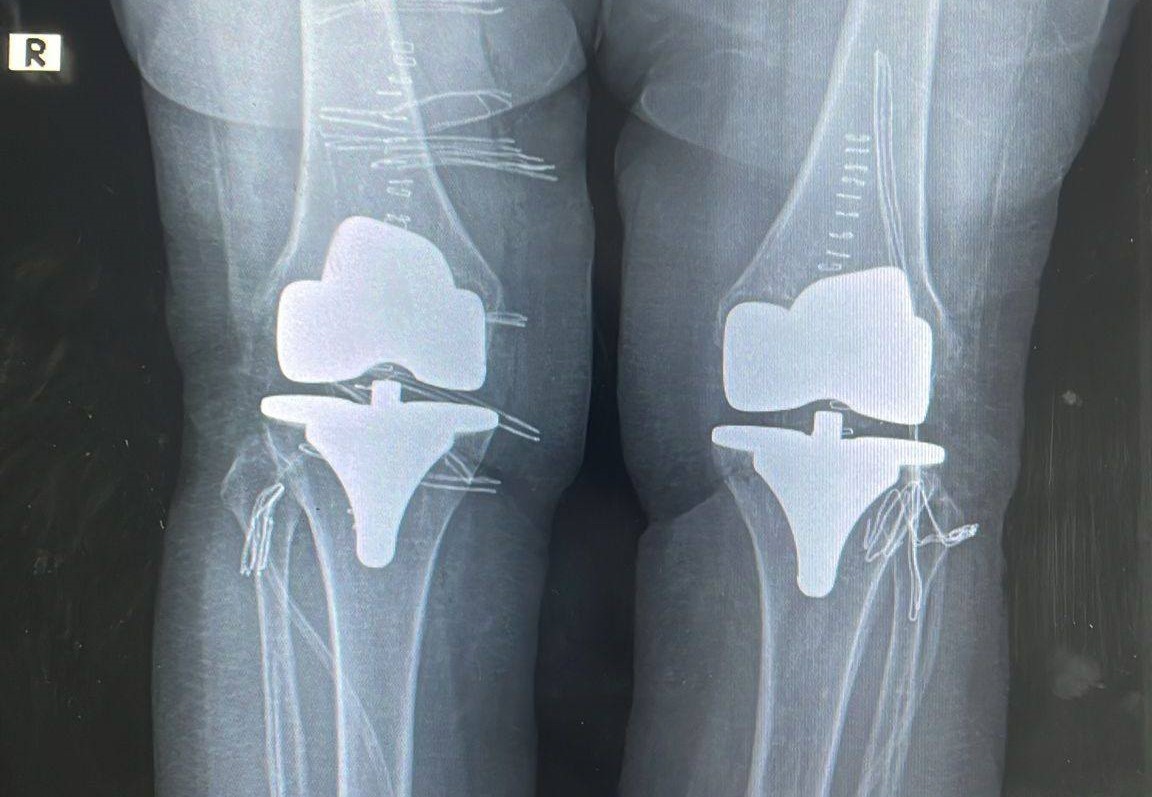

Bayburt Devlet Hastanesinde yapılan çift taraflı total diz protezi operasyonuyla 73 yaşındaki hastanın dizlerindeki ağrı giderildi. Başarılı geçen ameliyatla hasta sağlığına kavuştu.

Ortopedi polikliniğine dizlerindeki yoğun ağrı şikayetiyle başvuran 73 yaşındaki hastanın her iki dizinde ileri derecede kireçlenme tespit edildi. Ortopedi ve Travmatoloji Uzmanı Op. Dr. Reşat Arıkan tarafından gerçekleştirilen operasyonda, hastanın her iki dizine çift taraflı total diz protezi uygulandı. Tek seferde yapılan ve başarılı geçen bilateral ameliyatının ardından hastanın sağlık durumunun iyi olduğu öğrenildi.